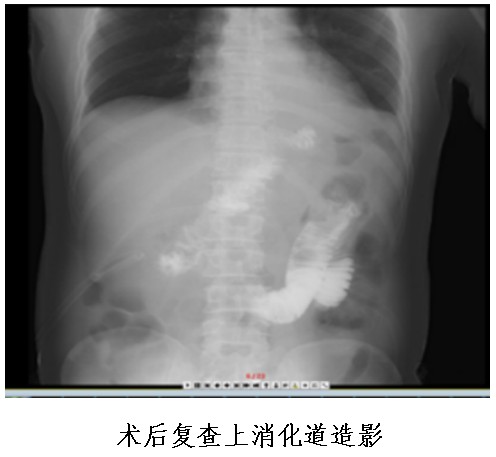

普外中心主任兼胃腸外科主任譚曙光組織醫(yī)師團(tuán)隊(duì)就患者治療方案進(jìn)行討論,認(rèn)為該名胃體神經(jīng)內(nèi)分泌瘤患者,符合手術(shù)指征。經(jīng)過(guò)反復(fù)評(píng)估并與患者本人及家屬溝通,最終譚曙光醫(yī)師團(tuán)隊(duì)決定摒棄傳統(tǒng)的胃切除術(shù),選擇腹腔鏡根治性近端胃切除+D2淋巴結(jié)清掃及雙通道吻合(食道空腸over-Lap吻合及空腸遠(yuǎn)端胃吻合)術(shù),有效減少了反流性食道炎等術(shù)后并發(fā)癥的發(fā)生。1月9日,患者完成了手術(shù),術(shù)后恢復(fù)順利并于22日出院。

①食管空腸吻合口;

②殘胃空腸吻合口;

③空腸空腸吻合口。

其中,食管空腸吻合口距殘胃空腸吻合口15-20cm,殘胃空腸吻合口距空腸空腸吻合口15—20cm。

食物通過(guò)食管空腸吻合口后,一部分通過(guò)胃空腸吻合口進(jìn)入遠(yuǎn)端胃、十二指腸及小腸,另一部分食物直接進(jìn)入小腸,故稱(chēng)之為“雙通道”消化道重建。

該吻合方式通過(guò)增加了一個(gè)殘胃與小腸的食物通道,可以防止胃酸直接反流進(jìn)入食管,而遠(yuǎn)端胃和原有消化通道的保留,可以維持胃與十二指腸的部分功能,成功解決近端胃切除術(shù)后患者胃食管返流、胃癱及遠(yuǎn)期營(yíng)養(yǎng)障礙的問(wèn)題,大大提高術(shù)后患者的生活質(zhì)量。